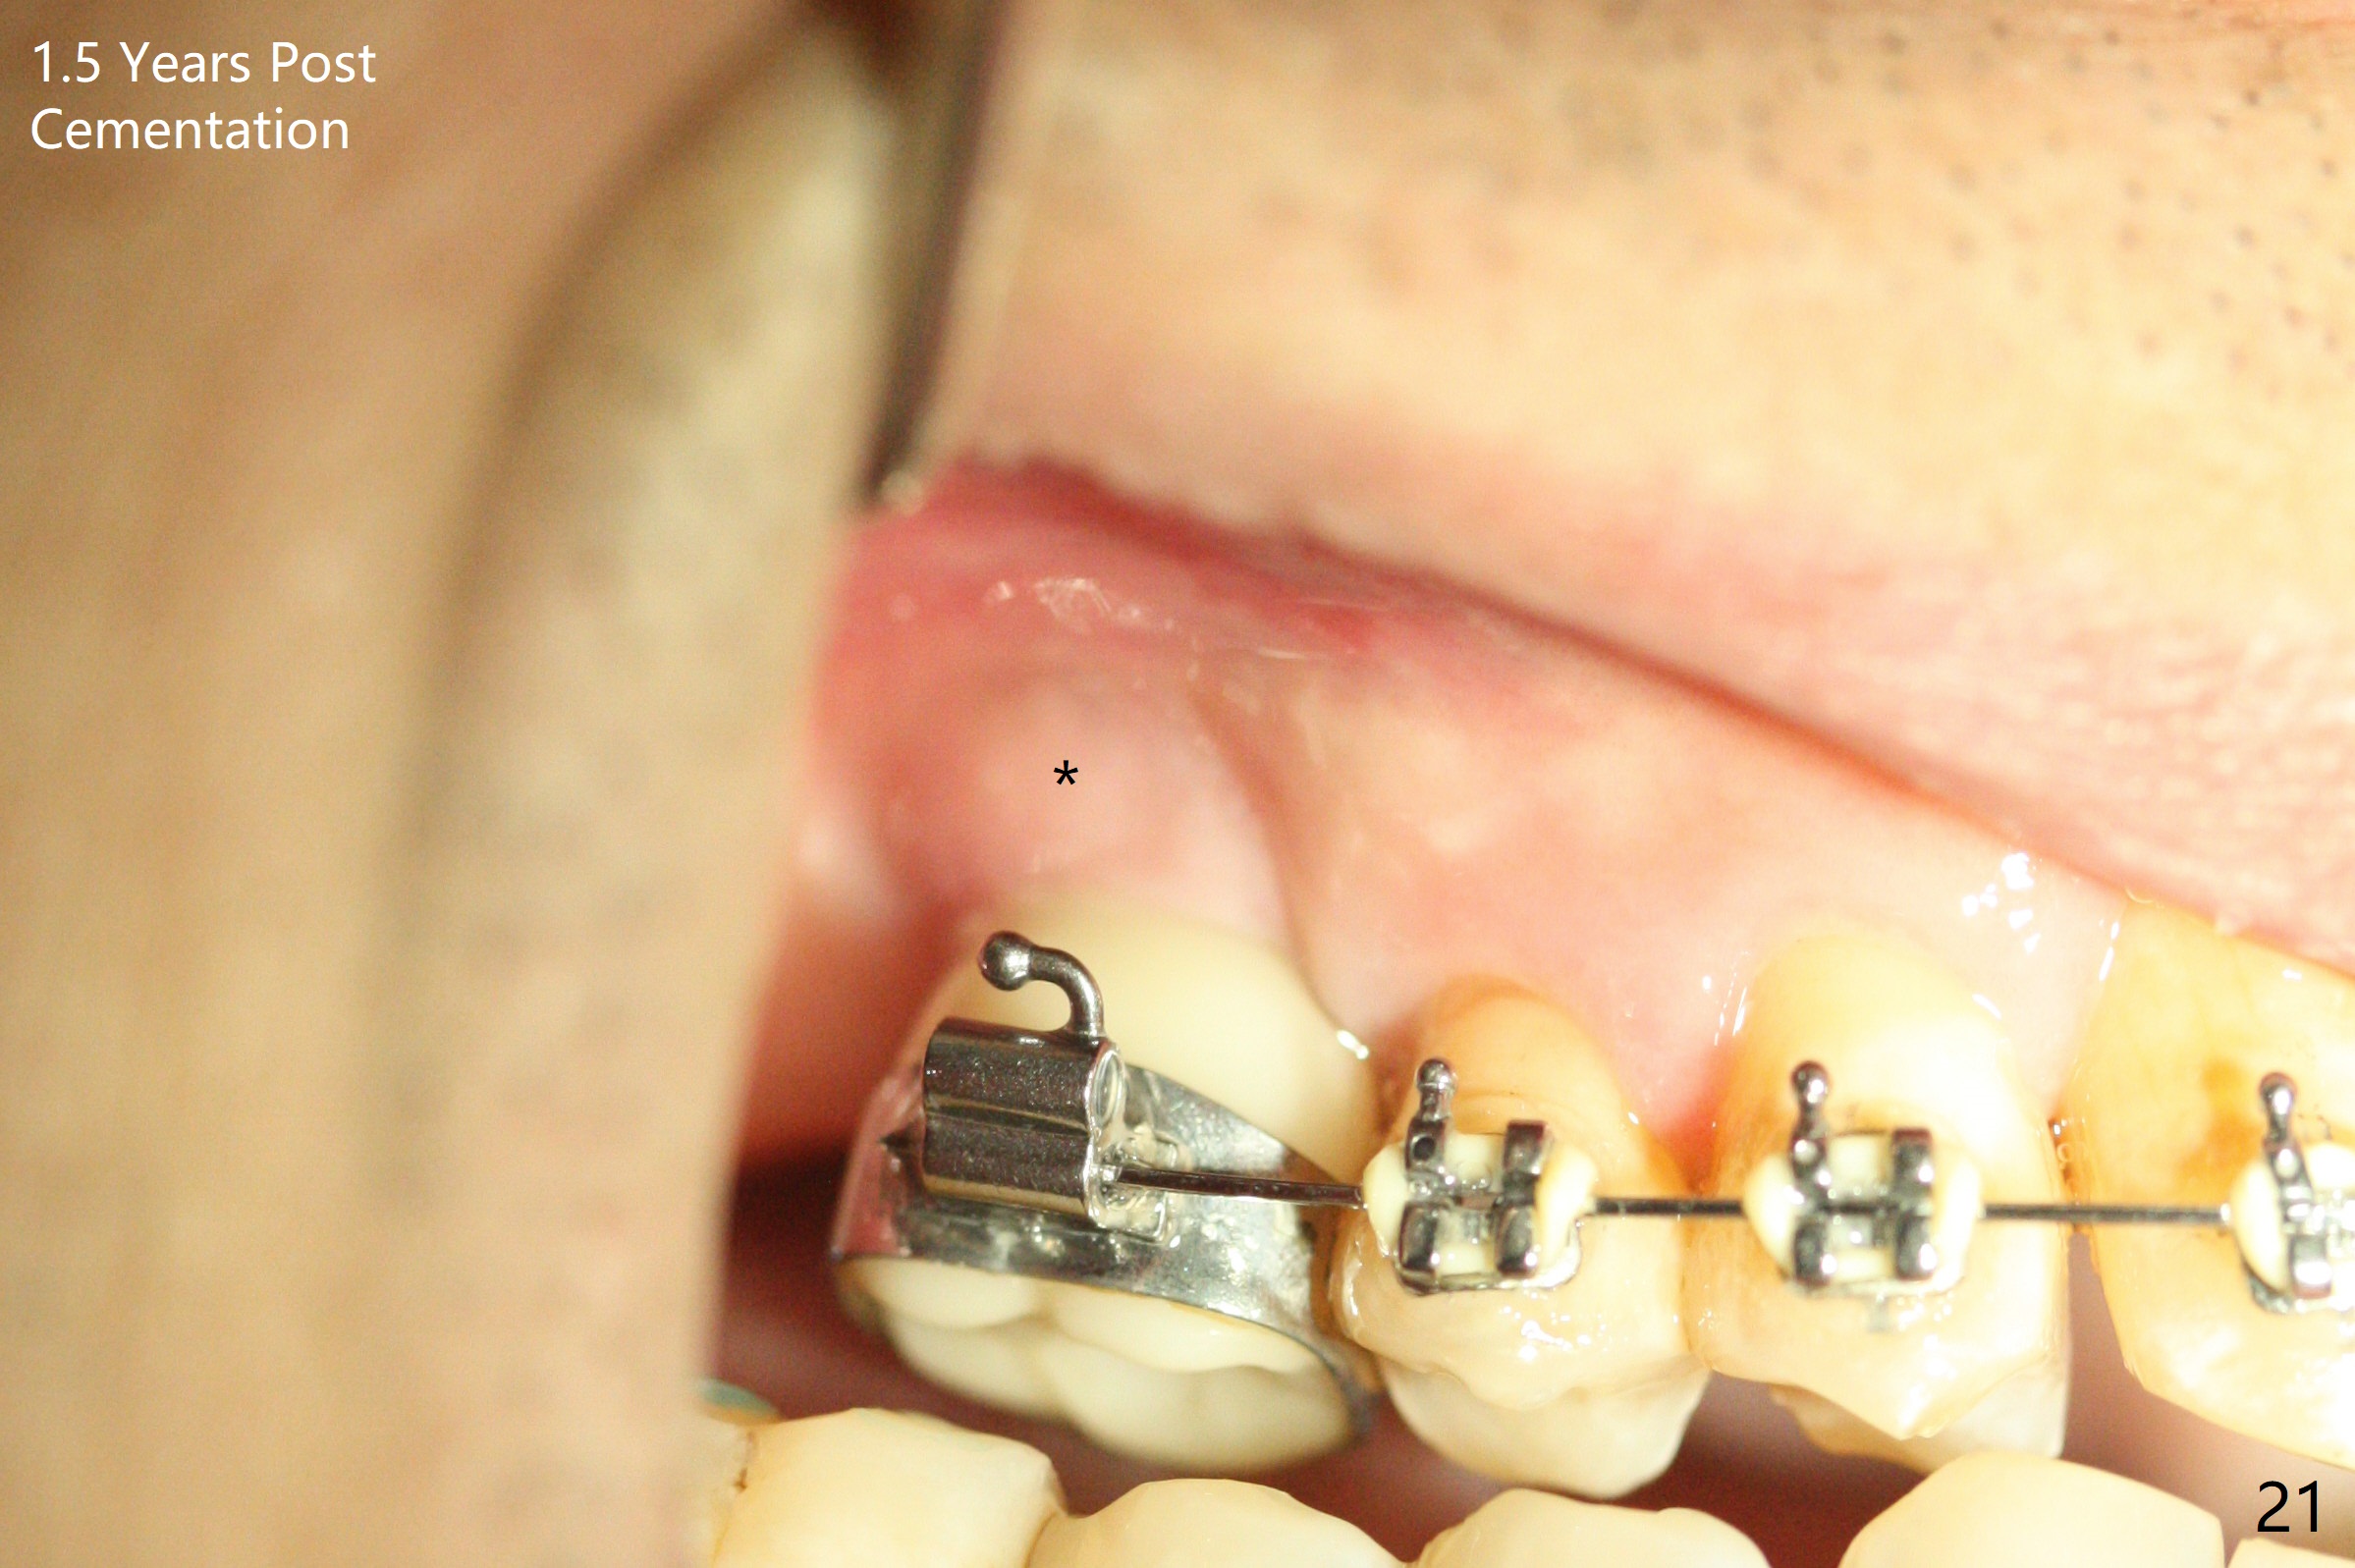

Two weeks later, the buccal gingiva appears to have grown downward (Fig.13). Fig.14 is taken when the provisional is removed. To facilitate this process, change abutment from 4.8x7(3) to (4.5) mm and a new provisional is fabricated (Fig.15): note the metal exposure distobuccally. When the patient returns in another two week, the gap should be able to disappear. There is no loss of bone graft 3 months postop (Fig.16). Two weeks later (3.5 months postop), the margin of the abutment is supragingival buccally and subgingival palatally (Fig.17,18). The gingiva seems to have migrated downward (Fig.19 arrow), while the bone density around the coronal implant appears to increase 5.5 months post cementation (Fig.20). There is buccal swelling with purulent discharge 1.5 years post cementation (Fig.21). Perimplantitis develops. Tuberosis bone graft will be performed when the limited ortho is finished.